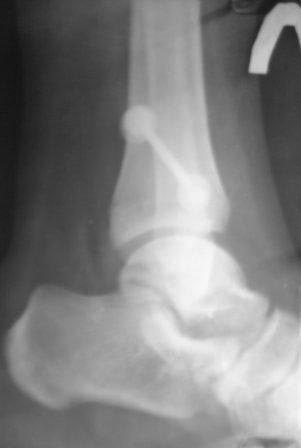

[Ortho] Последствие повреждений дистального межберцового синдесмоза

Нашлись еще снимки, сразу после операции и через год после операции, но снимков до операции не нашли.

Имя     : 2013-06-05-731 - ЛПРЙС.jpg

Имя     : 2013-06-05-732 - ЛПРЙС.jpg